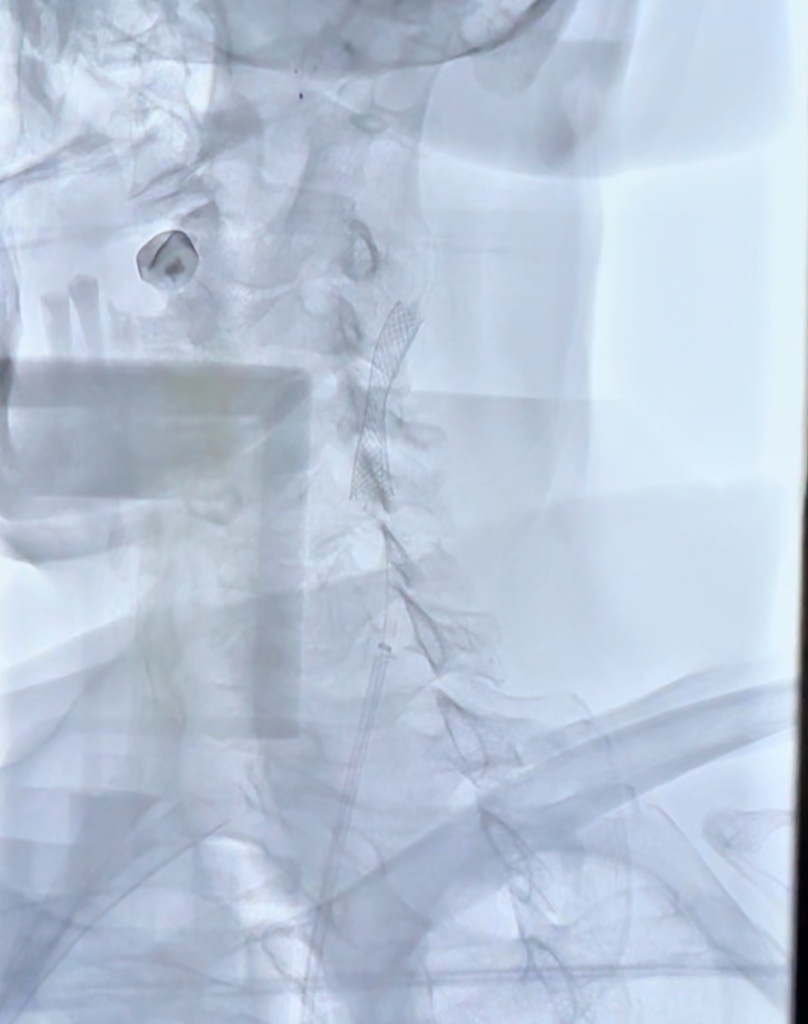

scale_1200 (3).jpg

Успешное выполнение стентирования сонной артерии